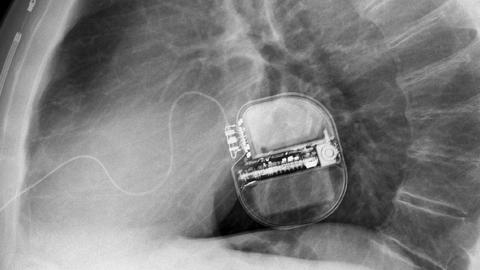

Röntgenbild von einem Defi

Die Implantation eines Defibrillators (ICD) erfolgt in der Regel unter lokaler Betäubung, verbunden mit einer leichten Narkose. Eine Vollnarkose ist nicht notwendig. Bei der Implantation wird nach gründlicher Desinfektion des Operationsbereichs zunächst die Vene zwischen Achsel und Schlüsselbein punktiert beziehungsweise freigelegt. Über diesen Zugang werden die notwendigen Sonden (zwischen einer und drei) unter Röntgendurchleuchtung ins Herz vorgeschoben und dort mittels eines Schraubmechanismus oder eines Ankers befestigt. Anschließend wird das ICD-Gerät in eine vorab geschaffene Gewebetasche ober- oder unterhalb des Brustmuskels eingebracht und mit den Sondern verbunden. Die Patienten können im Normalfall am Folgetag das Krankenhaus wieder verlassen.